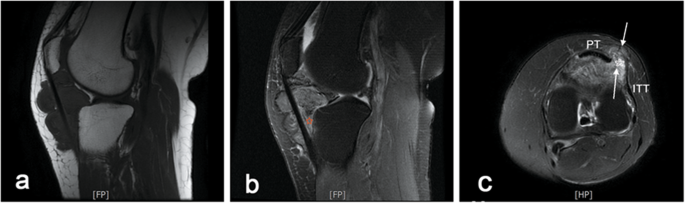

A 58-year-old woman who did not have a recent history of injury presented to our orthopaedic clinic with a tender palpable soft tissue mass in the anterolateral aspect of the left knee and acute reduced range of motion (ROM). The patient had a history of hyperuricemia for nearly 30 years and experienced knee trauma approximately 20 years ago. She complained of recurrent swelling and pain in the knee, which may have been misdiagnosed as gouty arthritis at the local community hospital because of similar symptoms. The advised treatment based on the symptoms, including colchicine and nonsteroidal anti-inflammatory drugs, partially relieved the patient’s symptoms. The physical examination showed moderate, recurrent swelling of the left knee without surrounding warmth, as well as a tender mass growing slowly in the anteroinferior aspect of the left knee. Because of pain, the patient’s ROM in flexion had decreased considerably (30° – 70° in the left knee, compared with 0° – 110° in the right knee). The results of the laboratory tests for both trioxypurine and infection were within the respective normal limits. The MRI examination of the left knee revealed a massive intraarticular soft tissue lesion (measuring 58 × 32 × 46 mm) that replaced the normal Hoffa fat pad and extended through the lateral patellar retinaculum (Fig. 1a and c). Moreover, the lobulated mass had a well-circumscribed margin and exhibited focal heterogeneous hypointensity representing the blooming artifact from haemosiderin (Fig. 1b), which is regarded as the pathognomonic appearance of PVNS on MRI. Only mild degenerative changes and joint effusion were observed, without tophus or bone erosion.

Preoperative MRI scans. a LPVNS manifested as a circumscribed and lobulated infrapatellar mass with an extra-articular extension through patellar tendon on sagittal T1-weighted images. b The pathognomonic appearance of PVNS, a “blooming artifact” caused by hemosiderin deposition (red pentastar), was observed on sagittal T2-weighted images. c Axial images revealed that extra-articular mass developed on both sides of the lateral patellar retinaculum, through a focal defect (asterisk), with a superficial component (arrowhead) and a deep component (arrowhead). ITT: Indicates iliotibial tract; PT: patellar tendon